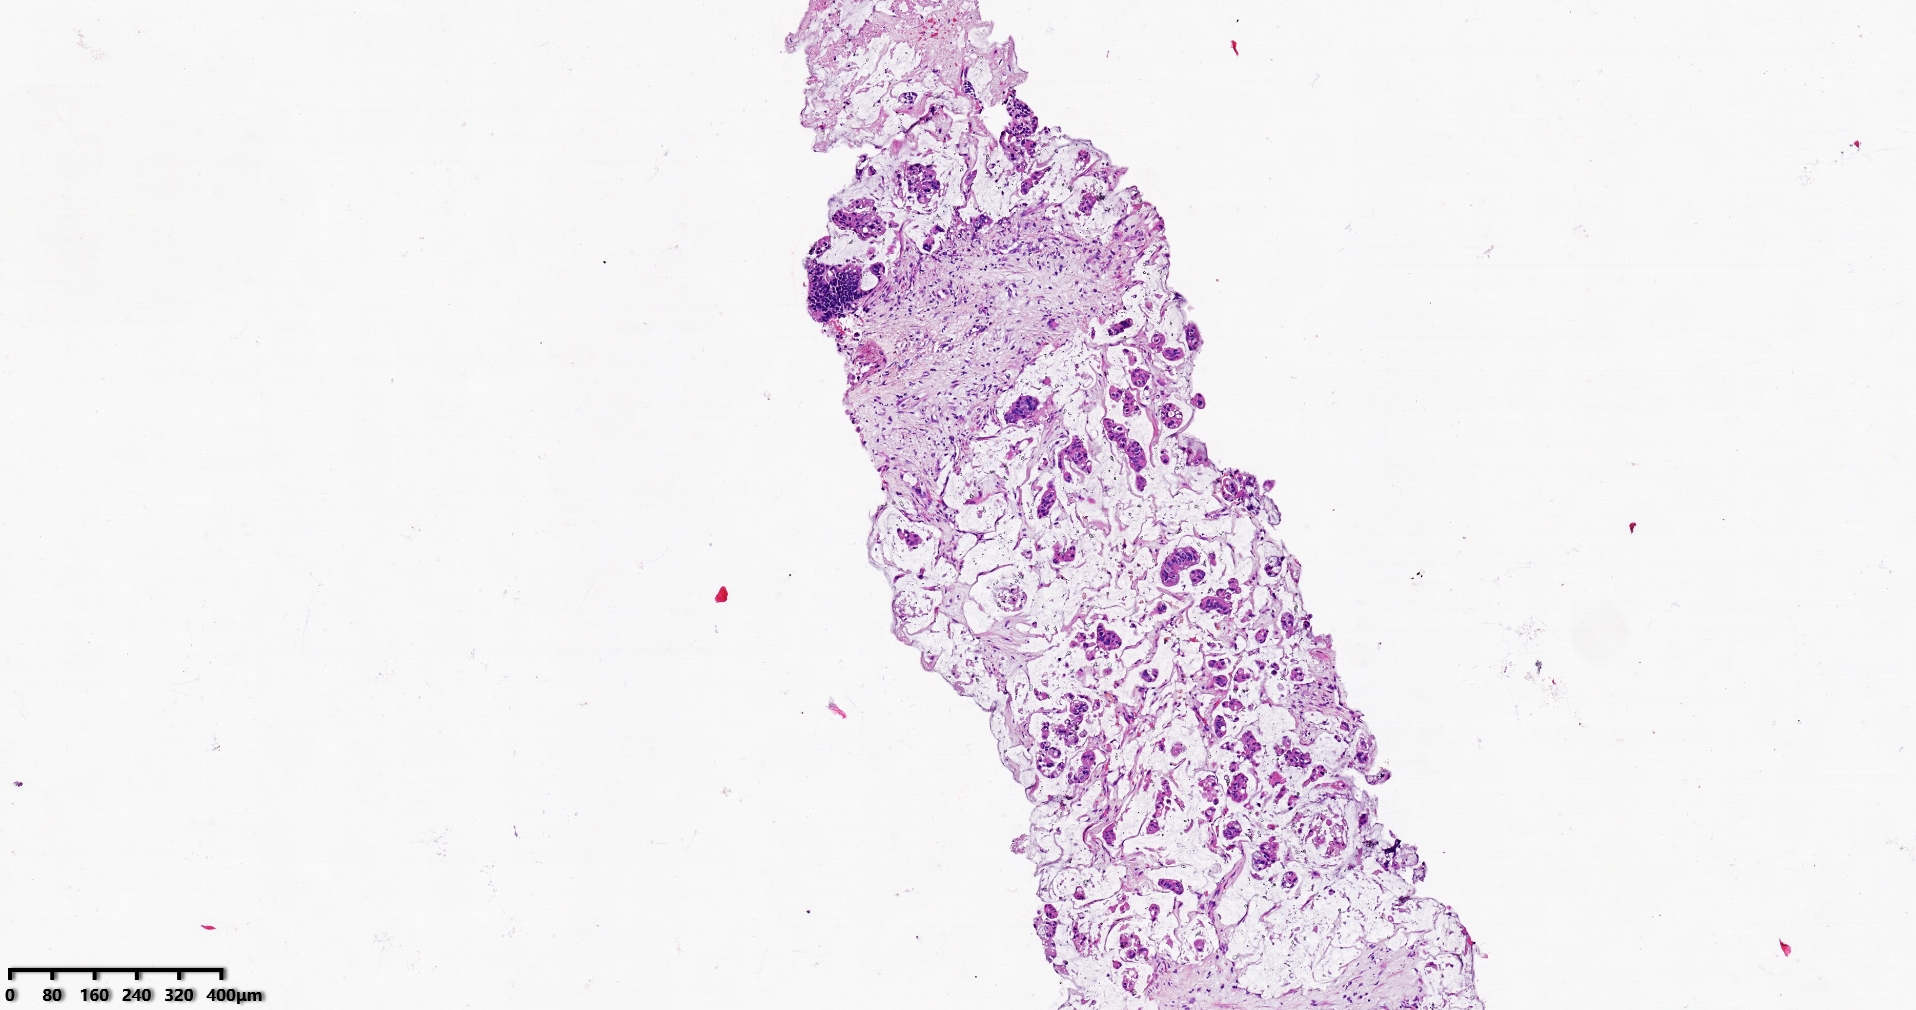

标本名称肝脏穿刺

大体所见灰白灰红色穿刺活检组织两条,长1.7-1.9cm,直径0.1-0.2cm。

考虑符合:肝内胆管癌

考虑转移性黏液腺癌,消化道来源可能,建议做免疫组化,排除胆管源性。